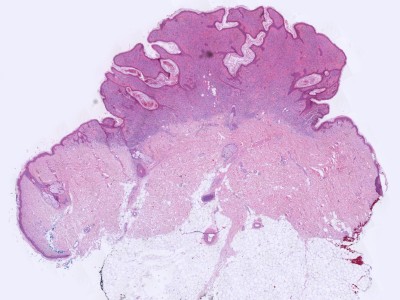

![Histologie naevus naevocellularis papillomatosus (click on photo to enlarge) [source: Kevin Kwee / Afdeling Pathologie MUMC] Histologie naevus naevocellularis papillomatosus](../../../pacoupes/thumbnails/naevus-naevocellularis-papillomatosus-1.jpg) |

![Histologie naevus naevocellularis papillomatosus (click on photo to enlarge) [source: Kevin Kwee / Afdeling Pathologie MUMC] Histologie naevus naevocellularis papillomatosus](../../../pacoupes/thumbnails/naevus-naevocellularis-papillomatosus-2.jpg) |

![Histologie naevus naevocellularis papillomatosus (click on photo to enlarge) [source: Kevin Kwee / Afdeling Pathologie MUMC] Histologie naevus naevocellularis papillomatosus](../../../pacoupes/thumbnails/naevus-naevocellularis-papillomatosus-4.jpg) |

ingescande coupe (zoom) |